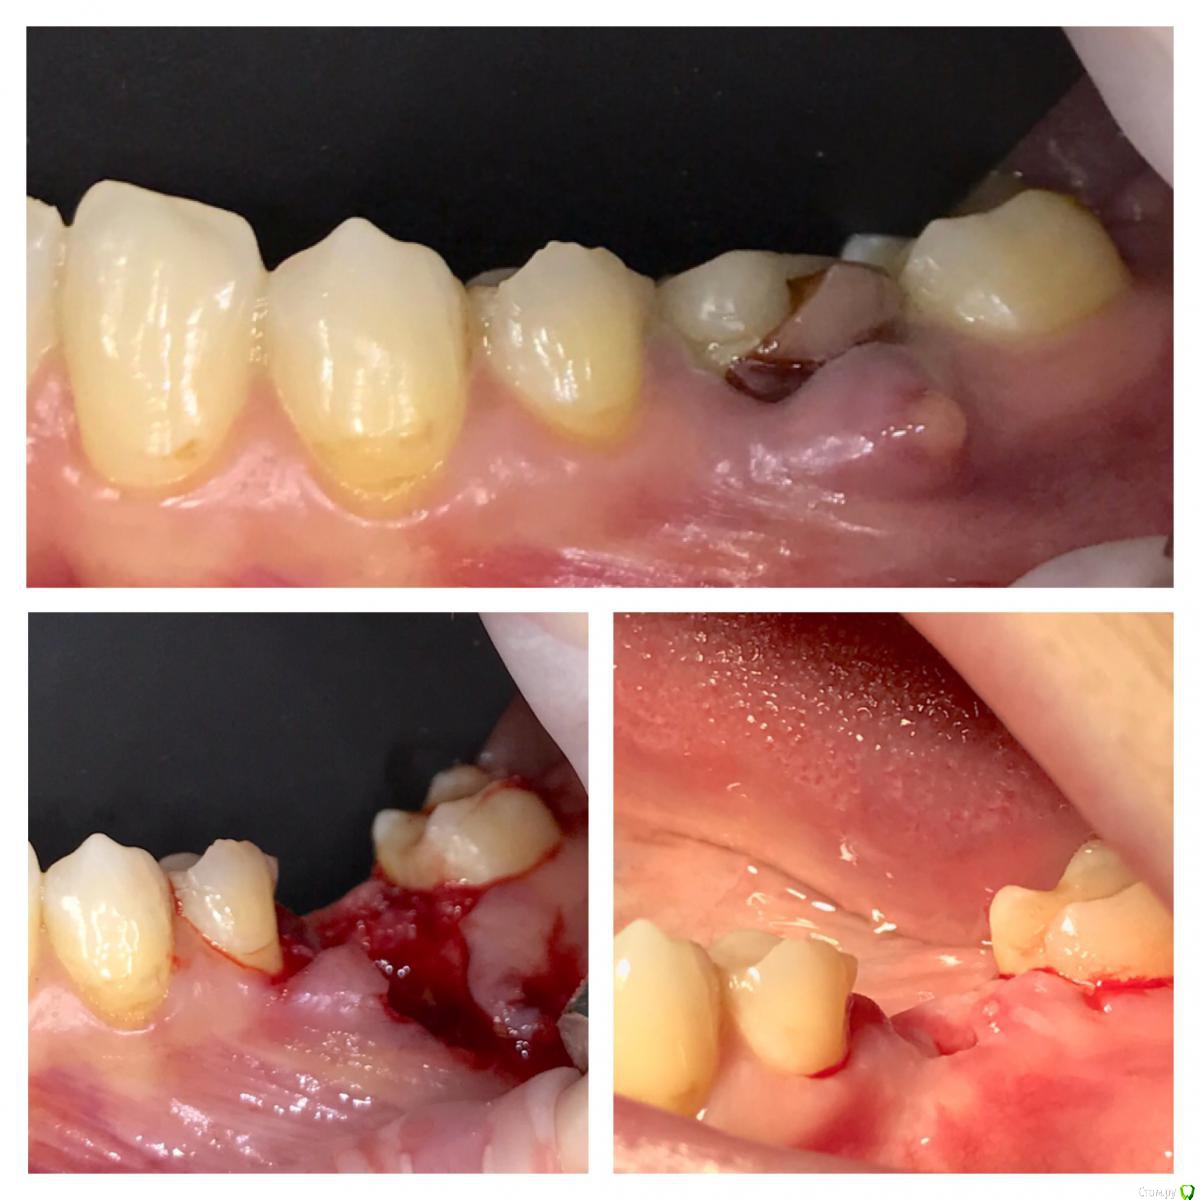

колесников Опубликовано 22 апреля, 2019 Поделиться Опубликовано 22 апреля, 2019 (изменено) И снова профайл спасает жизнь (облегчает жизнь имплантолога)Стандартная ситуация:36 периодонтит в стадии обострения с грануляциями,эксудацией,резорбцией компактной пластинки,дефицитом прикреплённой слизистой вестибулярного. Одна хирургия. Ноябрь 2018. Удаление,кюретаж,имплант Astra tech profile 4.5x9 под заглушку,торк около нуля. Вестибулярного сст,консервация графтом Sureoss 0,5 чипс с APRF,закрытие шайбой по Ноймайеру. Через неделю шайба несостоятельна-удалена. Пациентка созрела на удаление 37го. Выполнена декоронация в связи с отъездом пациентки,далее через 2 недели удаление и имплантация 37го. Промежуточный осмотр в январе. В марте установлены формирователи . Апрель контрольный осмотр. Периотест -5. Направлена на протезирование. Изменено 22 апреля, 2019 пользователем колесников 4 Ссылка на комментарий

колесников Опубликовано 23 апреля, 2019 Автор Поделиться Опубликовано 23 апреля, 2019 Разница от платформы до зенита 3 мм.Ещё раз. Вестибулярно дефект 9мм. Полное отсутсвие прикреплённой слизистой,язычное поднутрение и воспалительный процесс. Чтобы провести олномоментную имплантацию пришлось бы взять короткий имплант,заглубить его на 8мм от зенита,засыпать графтом,перекрыть мембраной,натянуть щеку и ждать-молиться чтобы края не разошлись и все не стухло. А после 2 -3 десневые пластики и глубокая шахта. Господа! Коллеги! Где сроки? Где бюджет? Где прогнозы? Ладно имплант и его глубина, это не так существенно,я вам показал как из ничего за 1 визит получить кератинизированую и прикрепленную слизистую без основания Ссылка на комментарий

колесников Опубликовано 24 апреля, 2019 Автор Поделиться Опубликовано 24 апреля, 2019 Для чего нужно асл при одномоментной имплантации с бешенным дефицитом десны? Чем "теория десневых каркасов" отличается от классической методики костной регенерации кроме отсутсвия коллагеновой мембраны в целях экономии?Как можно считать одномоментную имплантацию с нкр в инфицированной лунке в стадии обострения прогнозированным методом лечения?С уважением и благодарностью за то, что делитесь опытом и мнением!1)Асл конечно же 2ым этапом,после формирования аугментата2)классическая методика костной регенерации,точнее получений аугментата-это всеголишь одна из возможных составляющих будущего десневого каркаса. Вестибулярно маргинальная десна располагается на богатой коллагеном десневом валике,а тот в свою очередь на костном гребне (нативном или аугментате), который в свою очередь питается от этого валика. Классическая нкр методика делает упор на объём кости,оставляя меньший объём десне. Есть чисто десневой каркас по гамборене. Но в этом варианте есть ограничения по вертикали. Мое предложение-дополнительные каркасные валики (зацепы) для поверхностной десны. В частности скос у профайла это дополнительный уступ для прикреплённой слизистой. Можно дополнительноиспользовать супрастуктуры а качестве поддержки. Мне удавалось делать каркас высотой до 10мм без костной поддержки. После стимуляции этого десневого каркаса,кость прибавляет в объёме 3) одномоментная имплантация всегда более прогнозируемая чем отсроченная. Питание по разному осуществляется и регенерация иначе происходит. Стерильной раны в полости рта не существует в принципе,отсрочено или одномоментно вы заходите. Прикорневая инфекция ограничена усиленной капиллярной сеткой,что благотворно сказывается на регенерации,наша задача :санация лунки и контроль вторичного инфицирования 2 Ссылка на комментарий